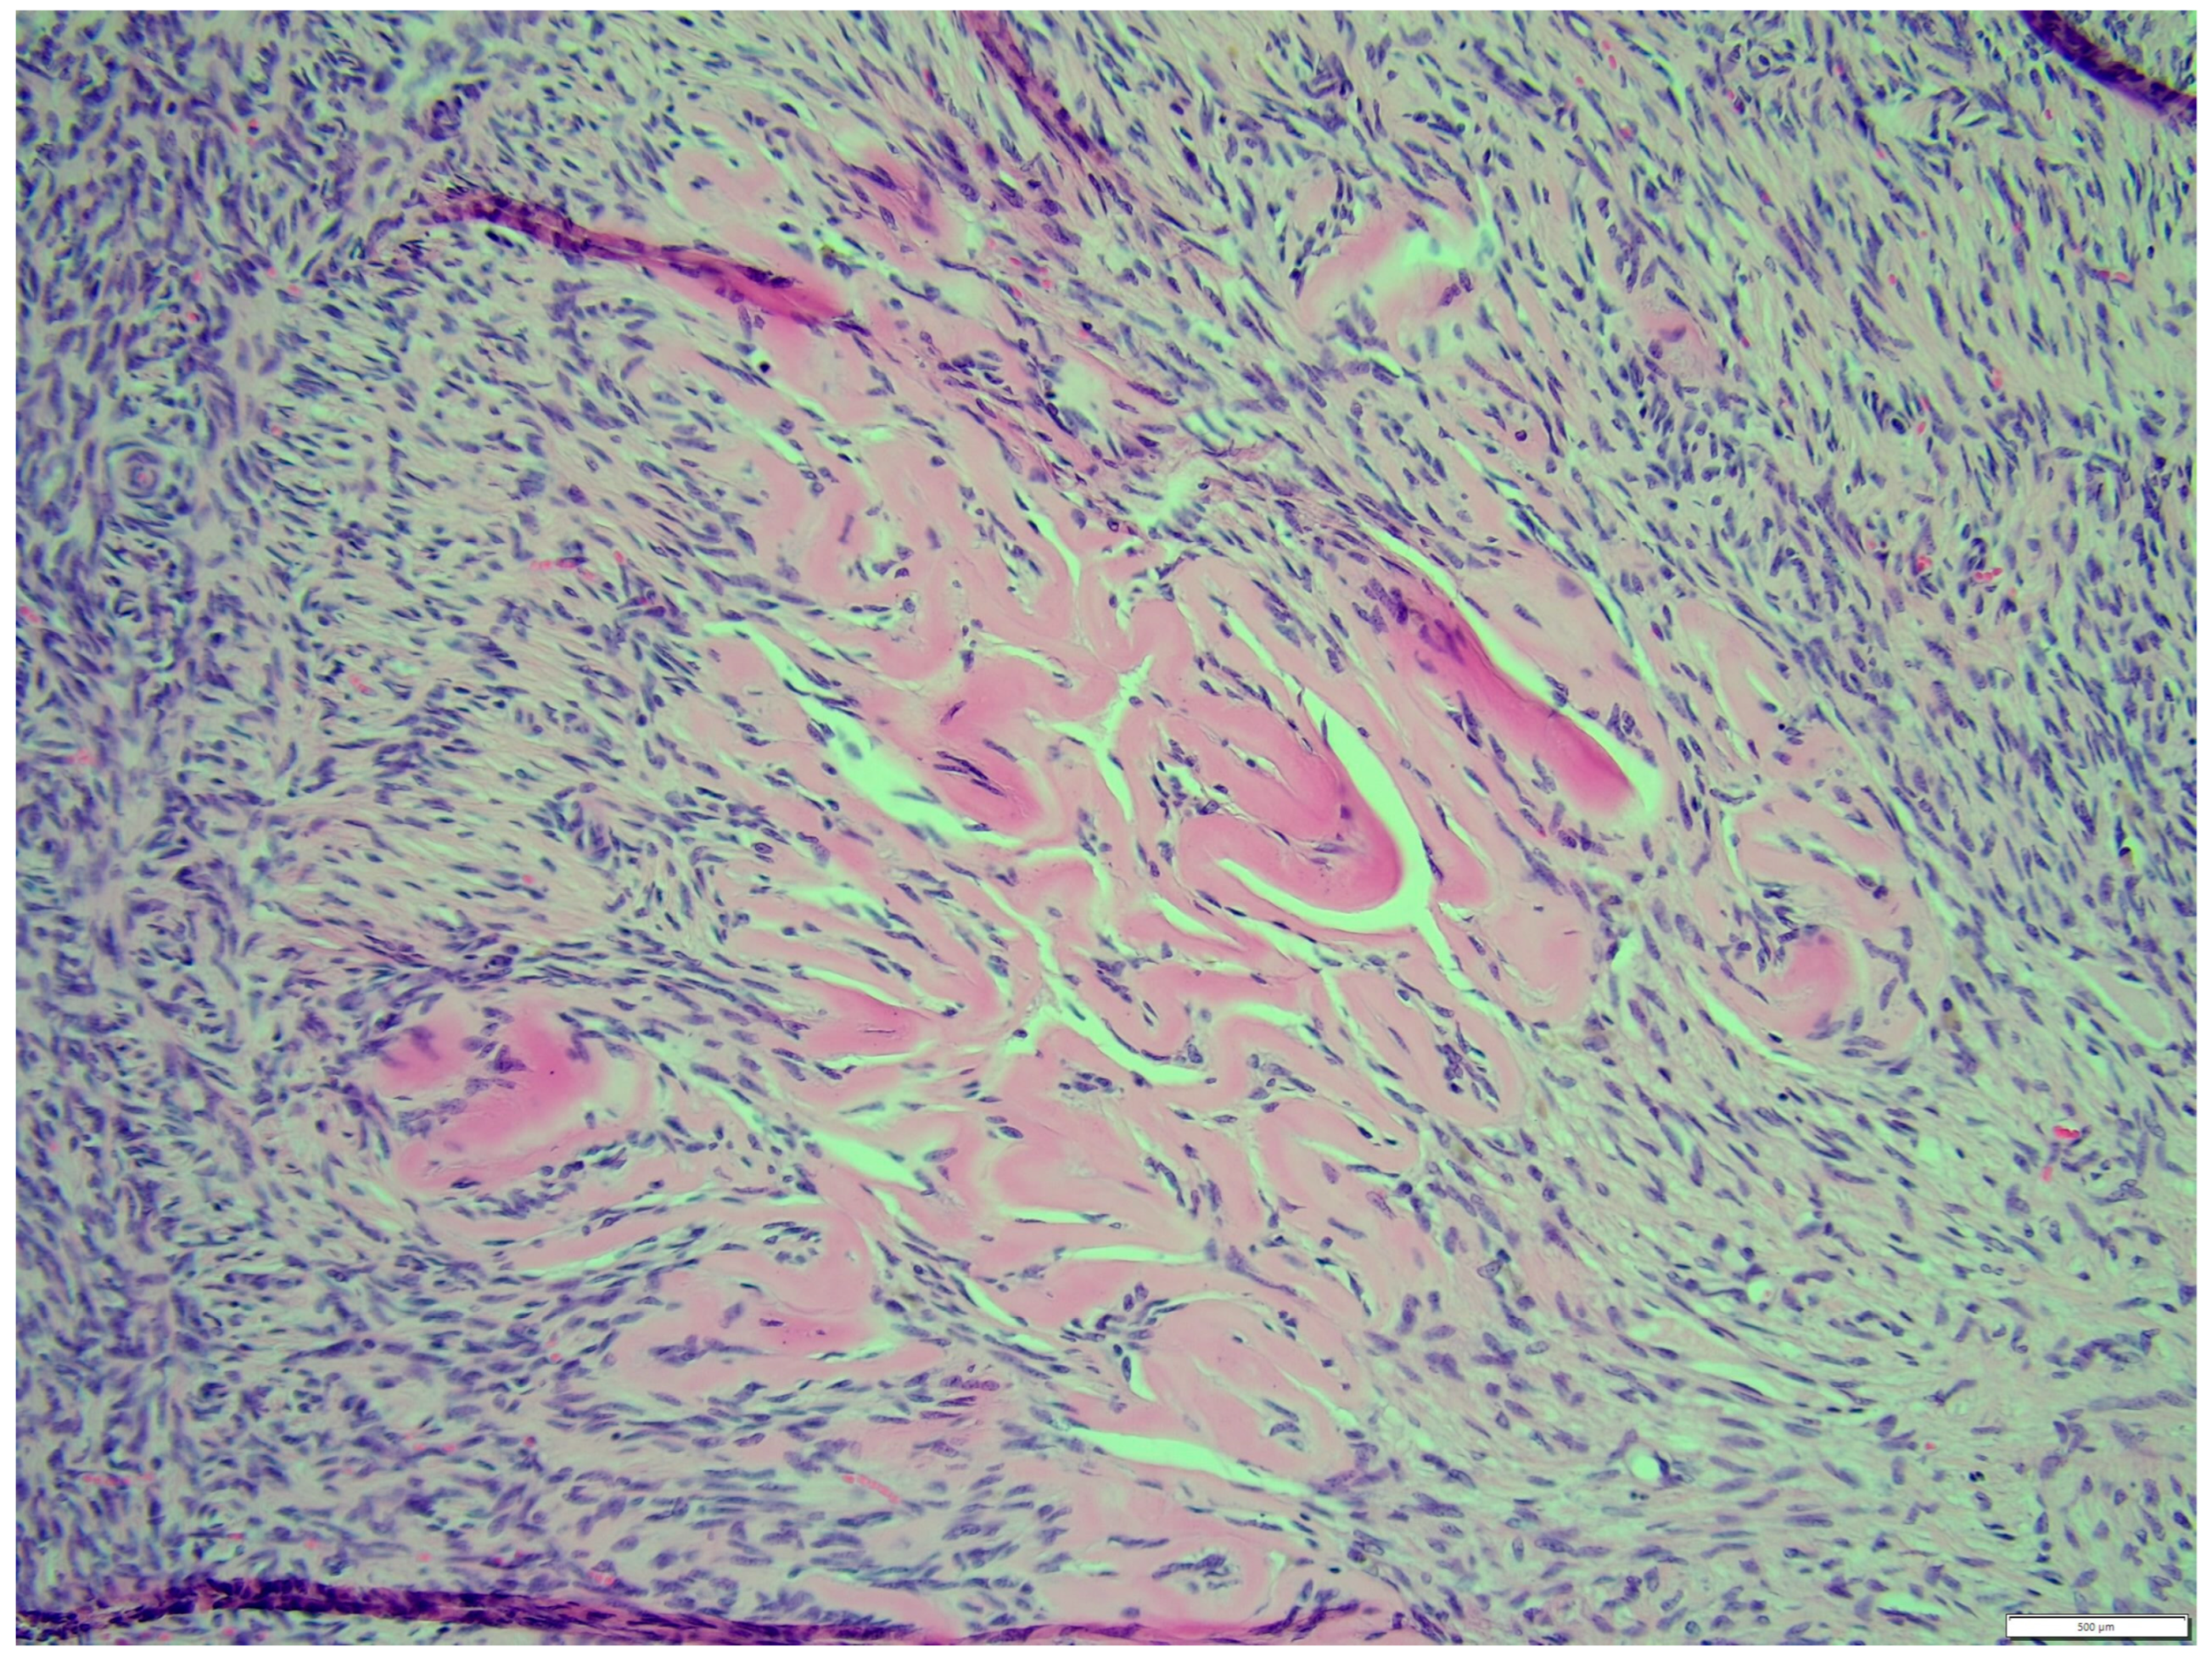

The fibroma was composed of uniform medium-sized, spindle-shaped cells with indistinct borders and a regularly shaped and sized oval, dark or gray nucleus to long thin nucleus cells. The indistinct nucleoli and finely stippled chromatin in the nucleus were observed. The nucleus/cytoplasm ratio favored the cytoplasm. The cytoplasm was pink and long, as is common in mature spindle cells. Spindle cell anisocytosis and anisokaryosis were mild to moderate (Figure 14). Mitoses were typical. The rate of mitoses was low—2 per 10 fields at 400 magnification. The spindle-like cells were arranged in sweeping fascicles angled in a chevron-like or herringbone pattern (Figure 15). In addition, storiform areas were observed (Figure 16). The stroma had a delicate intercellular network of collagen, but a few areas of “keloid-like” sclerosis/hyalinization were found (Figure 17). The histological pattern is typical for fibrosarcoma, but not for fibroma. However, tumor cells lacked marked atypia. The ovary-derived fibroma was considered to be a pure stromal tumor of the ovary.

Figure 15. The spindle like cells were arranged in sweeping fascicles that are angled in a chevron-like or herringbone pattern, fibroma part. HE, 200× magnification.

Animals 14 01307 g015